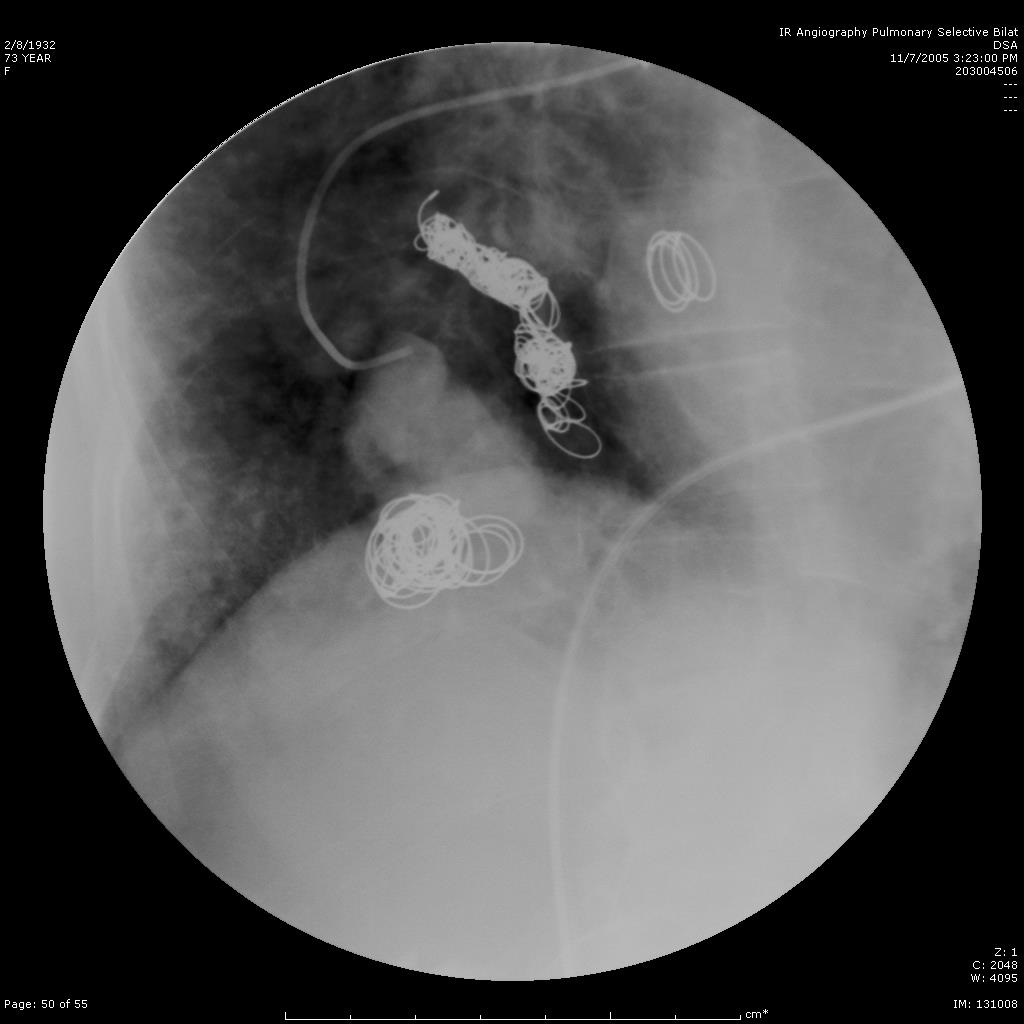

选择性肺动脉造影显示另一支滋养动脉和静脉池。 |

|

|

|

|

选择性进入滋养动脉 |

栓塞后弹簧栓子逸出至右肺静脉 |

栓塞后弹簧栓子逸出至右肺静脉 |

|

|

|

|

|

弹簧栓子在左心房“狂”跳 |

没啦? |

|

|

|

|

去哪儿啦? |

在这儿! |

造影 |

|

|

|

|

嵌在股深浅动脉分叉处 |

弹簧栓子被移除 |

继续栓塞 |

|

|

|

|

研究静脉池出口情况 |

寻找最佳工作位 |

静脉池出口直径大 |

|

|

|

|

静脉池出口直径大 |

放弃静脉池栓塞,仅栓塞滋养动脉 |

完成任务 |